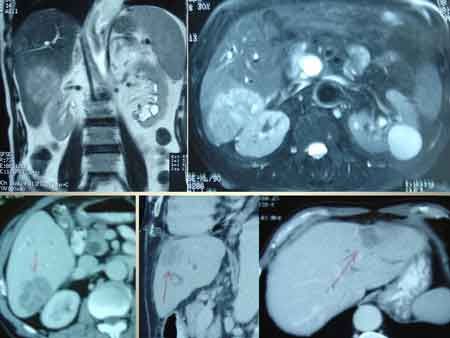

MRI done on the next day showed dilatation of the CBD (common bile duct). There is a round mass lesion in the lower end of the CBD protruding into the duodenum. Impression: biliary obstruction due to a polypoid mass arising from the lower end of CBD — ampullary tumour ?

CT showed a soft tissue mass at the ampulla of vater measuring 2.1 cm x 2.2 cm. The common bile duct is also dilated with greatest diameter measuring 2.3 cm. LY’s problem was diagnosed as cancer of the ampulla with biliary obstruction. There is no evidence of liver metastasis.